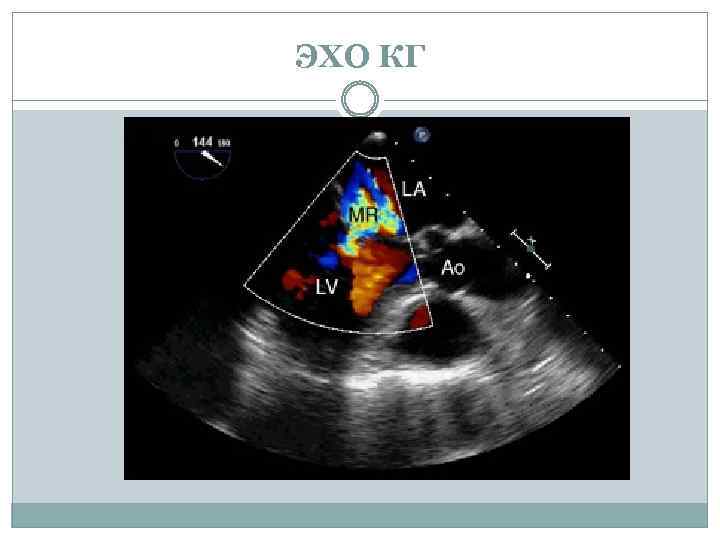

ЭХО КГ

ЭХО КГ